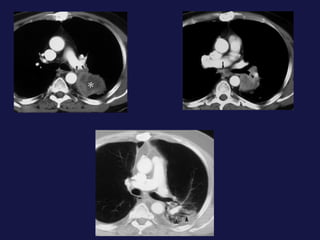

Carcinoma de células pequeñas   (18-25%). Peor pronóstico en  cuanto a supervivencia, responde bien a la quimioterapia. Variedad que mas da smes paraneoplasicos. 90% en bronquios centrales. SME de la vena cava superior. Localización central.

Extensión local y a distancia. Afectación  hiliar Invasión de la pared torácica (Pancoast). Afectación  pleural ( 8-15%). Afectación mediastínica. Linfangitis carcinomatosa. Metástasis extratorácicas.

Carcinoma de célulaspequeñas (18-25%). Peor pronóstico en cuanto a supervivencia, responde bien a la quimioterapia. Variedad que mas da smes paraneoplasicos. 90% en bronquios centrales. SME de la vena cava superior. Localización central.

Extensión local ya distancia. Afectación hiliar Invasión de la pared torácica (Pancoast). Afectación pleural ( 8-15%). Afectación mediastínica. Linfangitis carcinomatosa. Metástasis extratorácicas.